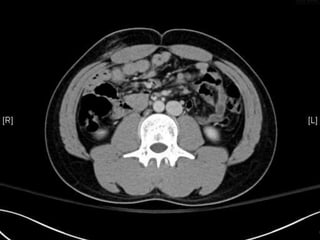

• CT:

 Shanmuganathan(2004)

 Sen:97%, spe:98%, accuracy:98% in penetrating stab wds

 Velmahos(2005)

 GSW: Sen 90.5, Spe: 96%

Radiology 2004:231:775-784

J trauma 2005:59:1155-1161